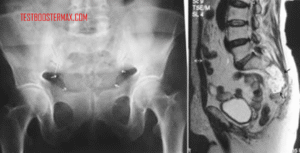

Diagnosis LMA dilakukan melalui pemeriksaan darah lengkap, biopsi sumsum tulang, dan analisis sitogenetik. Pengobatan utama untuk LMA meliputi: